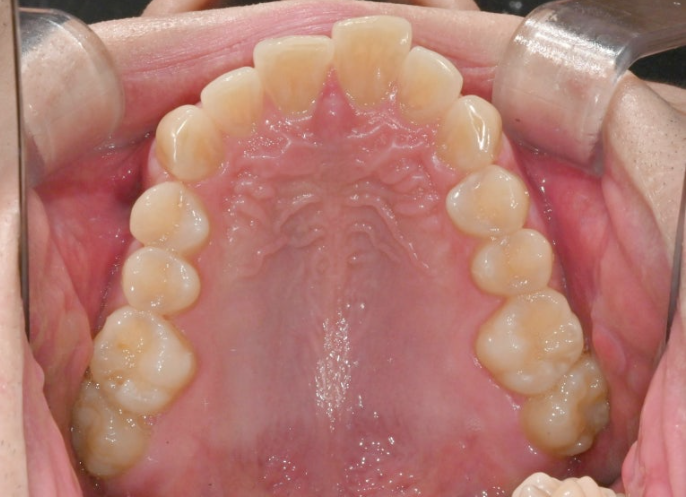

올해 초, 교정치료를 위해 내원한 30대 후반의 환자분입니다.

앞니가 깊게 물리는 과개교합.

중심선 불일치. 정도가 보입니다.

앞니가 많이 뻗쳐있습니다.

위 앞니 뻗침이 심하면 위 아래 앞니 사이 간극이 커지죠.

위아래 어금니 물리는 교합관계는 그래도 1급에 가깝습니다.

악궁모양이 약간 찌그러진 형태입니다.